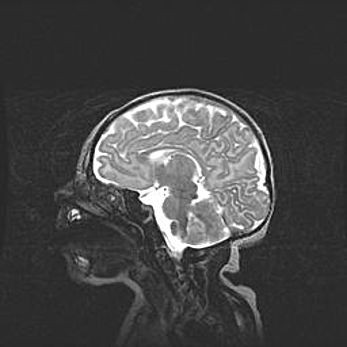

Церебральная ишемия II.

Возраст: 5 дней

Вес: 3400 г

Пол: женский

Окружность головы: 35 см

Срок гестации: 39 недель

Церебральная ишемия – это заболевание, характеризующееся недостаточностью (гипоксией) либо полным прекращением (аноксией) снабжения мозга кислородом по причине закупорки одного или нескольких сосудов. Это приводит к  что метаболическим расстройствам различной степени тяжести в тканях головного мозга, развитию коагуляционных некрозов и гибели нейронов.